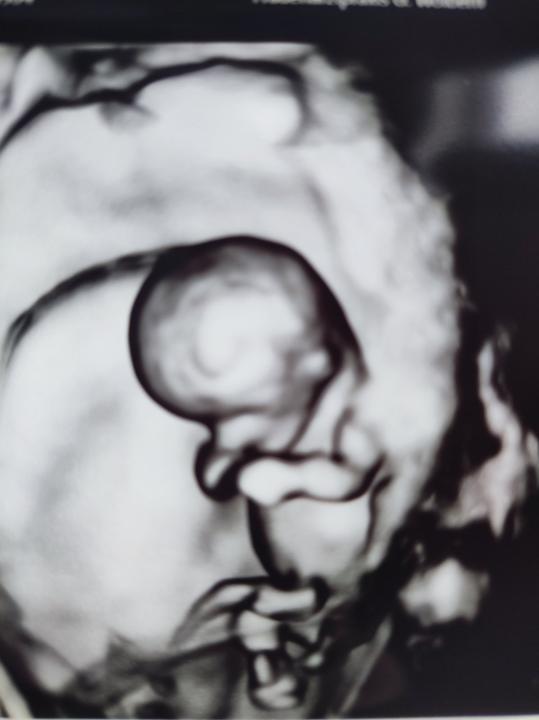

Kolko zazvoru - sackovy caj - je v tehotenstve v poriadku vypit? Som prechladnuta, bojim sa, ze sa to zhorsi, este len koncim 10.tyzden, takze lieky asi moc nehrozia... 1 salka? 2 salky? Na nete pisu 1-2g denne, ale to je cerstvy... Vdaka za kazdu radu.

Babulky,co na tehotenske nevolnosti? Nikdy sa ma to netykalo a myslela som,ze aj tentoraz nic. Ale posledne dni je to coraz horsie🫣 Neviem,ako takto budem fungovat v praci, nikto o tehu nic netusi🤰